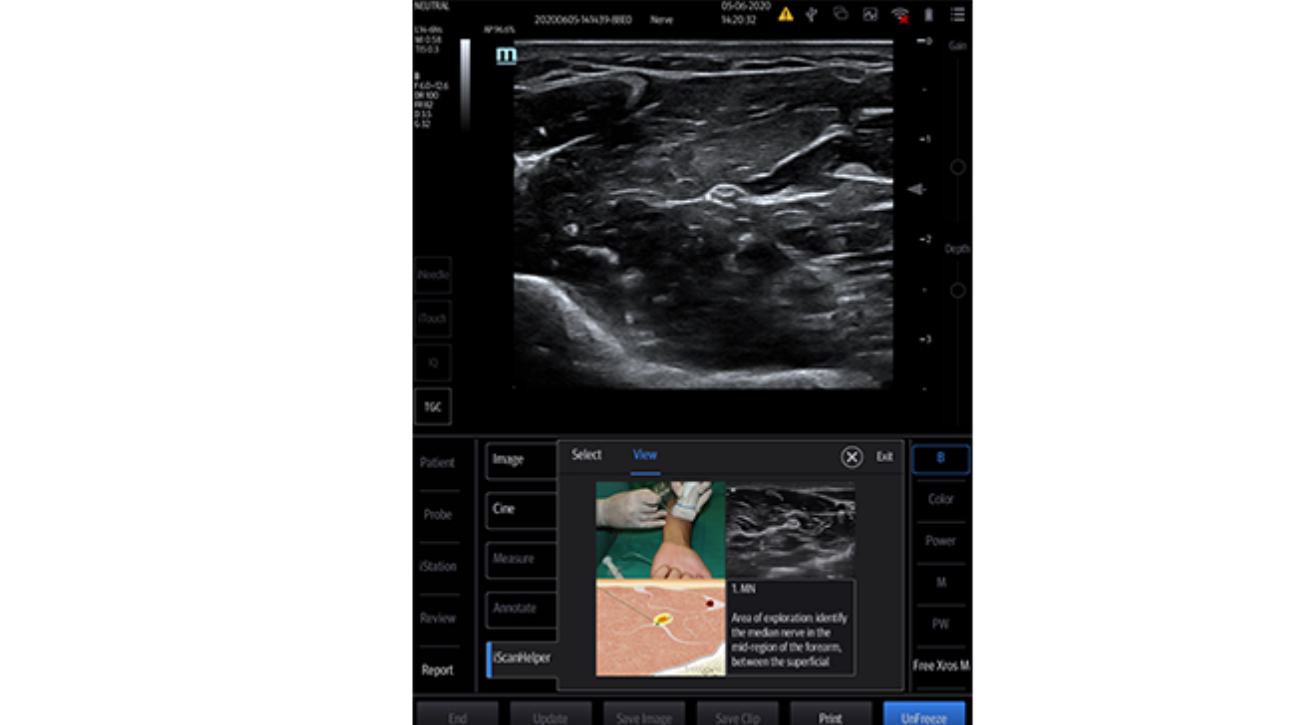

Esforzarse por una mejor atenciĂłn al paciente y buscar la mejor soluciĂłn para una decisiĂłn rĂĄpida es esencial para el personal clĂnico. Con herramientas inteligentes de gestiĂłn de fluidos, funciones para punciones seguras, una soluciĂłn completa de desinfecciĂłn e imĂĄgenes de calidad superior, el equipo Mindray TE7 ACE estĂĄ dise?ado para cubrir las aplicaciones de anestesia, cuidados crĂticos y emergencias. Listo para prestar atenciĂłn en cualquier momento, fĂĄcil de aprender y usar, ayuda a enfrentar con confianza todos los desafĂos de los servicios mĂ©dicos de alta calidad. Por primera vez, el TE7 ACE como ecĂłgrafo puede conectarse sin problemas a su red clĂnica con todos los demĂĄs equipos.